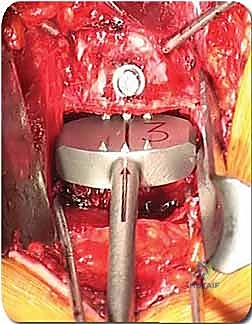

الخطوة 4: التحضير وزراعة القفص (Implant Insertion)

يتم قياس الفراغ المتبقي بدقة لاختيار الحجم المثالي للقفص الجراحي (Cage). يُصنع هذا القفص عادة من مادة PEEK أو التيتانيوم، ويتم حشوه بمادة عظمية (طعم عظمي ذاتي من المريض، أو طعم صناعي، أو بروتينات محفزة لنمو العظم BMP). يتم إدخال القفص بقوة في الفراغ، مما يؤدي فوراً إلى استعادة ارتفاع القرص الطبيعي وتوسيع المخارج العصبية (تخفيف الضغط غير المباشر).